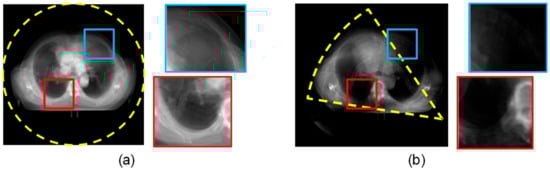

The fundamentals of CBCT imaging are the same as the CT; the difference between them is the sampling process during a scan. The CBCT is a special X-ray-based imaging technology. By a dedicatedly designed X-ray generator, the X-ray irradiation in a pyramidalis volume is mainly designed for dental imaging or for reducing the radiation damage in head scan, and the exposure dose is lower than the annular CT device [,,]. For the migrated CBCT which is applied to a body scan, the scan device only moves along the single direction of the z-axis without the rotation around the patient, so it is impossible to reconstruct an image with the same level of quality as the annular CT imaging. As Figure 9 shows, in some CBCT body scans, there are some areas where the data are obviously missing. An image of this quality is insufficient for diagnosis, but medical experts still use the advantage of a low exposure dose of the CBCT scan by image guide technology.

Figure 9.

(a,b) are the superposition of the CT and the CBCT sequences, the yellow dashed circle indicates the region with an abundant projection signal, and the rectangular boxes indicate two examples of missing data areas in the CBCT scan.

Considering that the fundamentals of CBCT and CT are the same, a pixel in a CBCT image has the same meaning as in the CT, even though the CT has accumulated added signal by more sampling angles; however, the value of the reconstructed image needs to be normalized in 0 to 255, the same as the range of a CBCT image. Therefore, for the area with better image quality in the CBCT sequence, the content is very similar to the CT image.